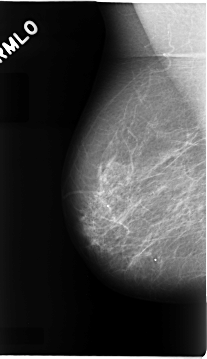

C_0072_1.RIGHT_MLO

LEFT_MLO LINES 4696 PIXELS_PER_LINE 2664 BITS_PER_PIXEL 12 RESOLUTION 50 OVERLAY

FILE: C_0072_1.LEFT_MLO.OVERLAY

LESION_TYPE MASS SHAPE LOBULATED MARGINS MICROLOBULATED

ASSESSMENT 5

SUBTLETY 5

PATHOLOGY MALIGNANT